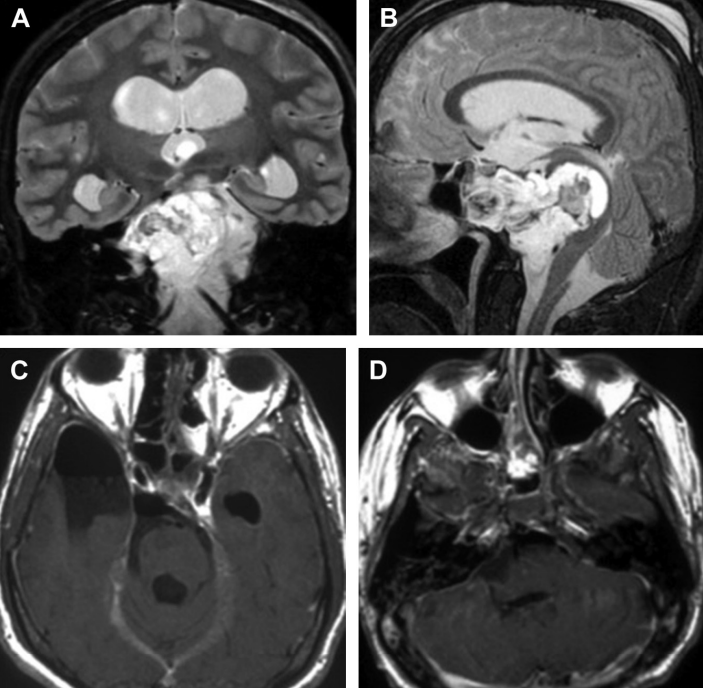

一名37岁的妇女因颈部疼痛和下颅神经功能障碍(声音嘶哑和吞咽困难)被咨询至我科。她先前被诊断出患有(CCJ) 颅颈交界处脊索瘤 ,并且先前在另一家医院进行了两次手术切除尝试...

法国一位37岁的女士因头痛、视力下降严重,到医院检查,被诊断出颅颈交界处(CCJ) 脊索瘤 。随后在一家比较医院治疗,该院采取了乙状窦后入路手术切除,但不久后,便再次复...